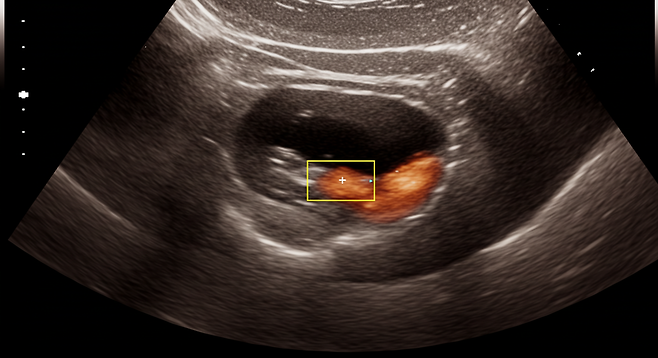

골반 덩어리

증상이 더 진행된 경우 골반에 덩어리가 만져지거나, 아랫배에 덩어리가 만져지기도 합니다.